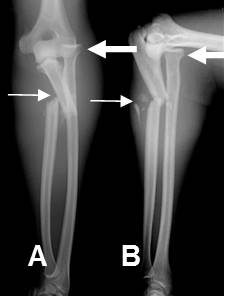

Fig 197. Fractura de Maisonneuve.

A: Rx lateral y B: Rx AP. Fractura espiroidea de la tibia y el peroné proximales, con diastasis de la mortaja tibio-peronea-astragalina, por lesión ligamentaria.